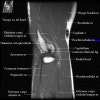

팔꿈치 관절의 MRI 단면 영상

2. Axial section

1) The tendons of the Biceps Brachii and Brachiallis muscles transversely as they insert onto the Radius and Ulna respectively. 2) The distal Triceps tendon is also well evlauated in this plane.